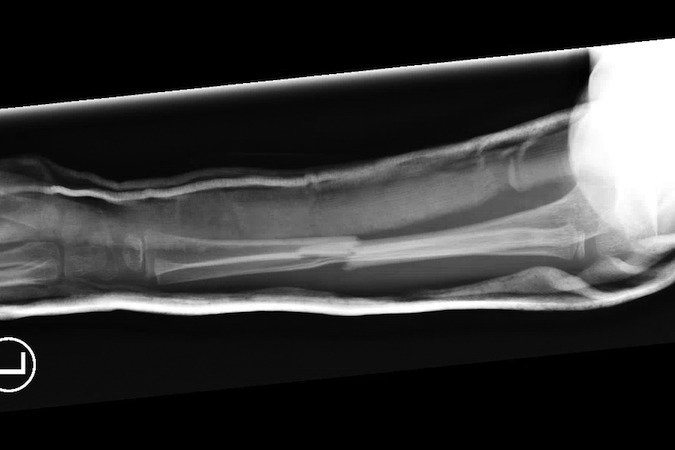

Greenstick fracture

- Pediatric forearm fractures are typically described as either complete or greenstick fractures.4

- Greenstick fractures are incomplete, partial thickness fractures in which only the cortex and periosteum are interrupted on one side of the bone but intact on the other side.4,18

- Greenstick fractures are more common among younger children under the age of 10 years, particularly boys, while completed or short oblique fractures are more common in older children.18,19

- The most common mechanism of injury is a fall on an outstretched hand (FOOSH), but other possible causes include car accidents, bike accidents, sports injuries, and non-accidental trauma.18